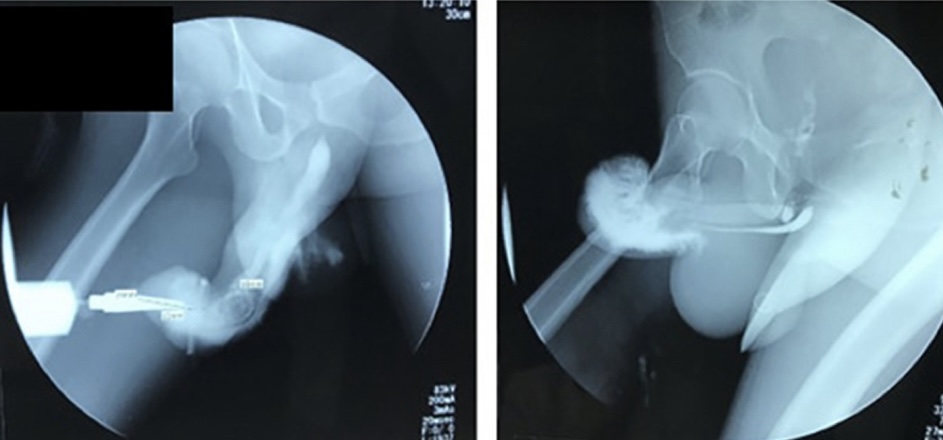

Un examen posterior reveló que su pene se había vuelto púrpura y se había desviado severamente hacia la derecha como un signo de interrogación, como se ve en las fotos gráficas incluidas en el estudio de caso.

Con el fin de volver a erigir el miembro deforme del hombre, los médicos abrieron el pene y arreglaron la uretra fracturada y el tejido del pene con puntos de sutura solubles, según el estudio. Luego drenaron el hematoma y luego probaron su función del pene con una «erección artificial».

Afortunadamente, el pene del paciente pasó el examen eréctil y no tuvo ninguna complicación, como fuga de líquido o un miembro doblado. Después de descansar en el hospital durante cinco días, el paciente fue dado de alta con un catéter uretral por el que se vio obligado a orinar durante los siguientes 21 días.

En una cita de seguimiento cuatro meses más tarde, el hombre dijo que estaba satisfecho con los resultados y que podía eyacular e «interactuar sexualmente con su esposa sin experimentar ninguna molestia», según el estudio. Aunque las fotos del chequeo revelaron que su virilidad todavía estaba ligeramente torcida.